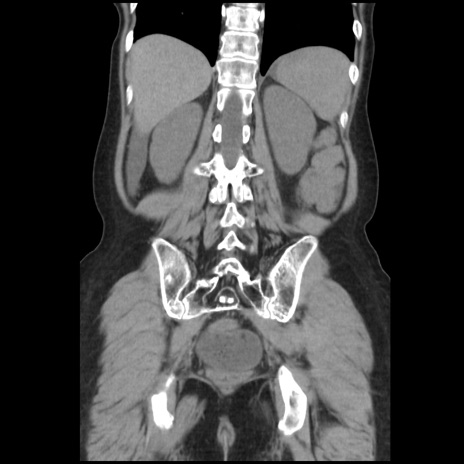

症例32(冠状断像)

【症例】40歳代 女性

【主訴】上腹部痛、嘔気・嘔吐

【現病歴】約9時間前頃から急に上腹部痛、嘔気、嘔吐が出現。改善しないため救急要請。

【既往歴】子宮頚癌(広汎子宮全摘術、放射線療法)、腸閉塞

【身体所見】腹部:平坦、軟、腸雑音亢進、上腹部を中心に腹部全体に圧痛あり。

【データ】WBC 8400、CRP 0.03